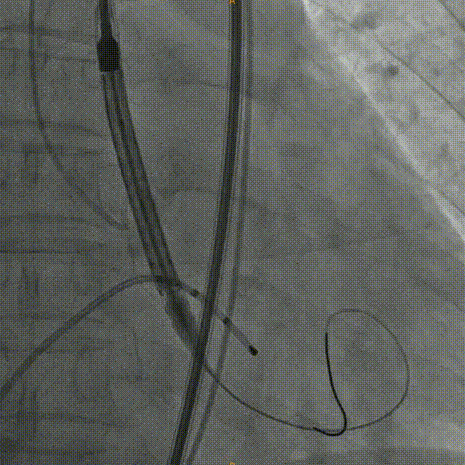

Venus26号瓣膜释放:前三分之一慢放精准定位,中三分之一快放使瓣膜快速进入工作状态。

Venus26号瓣膜释放:位置良好,轻度反流,遂完全释放后采取后扩。

后扩后瓣膜最终形态。